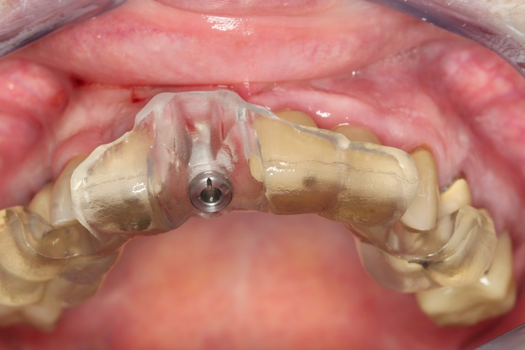

Fig 22. Abutment and PMMA positioned with PRF.

Figure 22

Fig 23. Provisional seated into position.

Figure 23

The provisional abutment and treatment crown were fabricated in the laboratory with the digital proposals. Platelet-rich fibrin (PRF) clot technology was incorporated to help with soft- and hard-tissue healing (Figure 19 through Figure 21). The screw-retained provisional and the PRF clot were seated immediately after implant placement (Figure 22 and Figure 23). One 4-0 polytetrafluoroethylene suture was placed to maintain papilla. The teeth immobilization splint was placed for 6 weeks (Figure 24). The rationale for splinting teeth Nos. 6 through 10 was due to noticeable plus-2 mobility of the remaining anterior teeth. The provisional implant crown also was included in the splint.